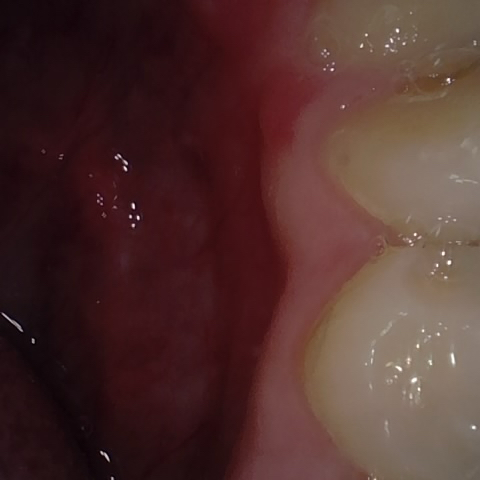

NHD20794

Annotated as "Good"

Original Image Rendering Image